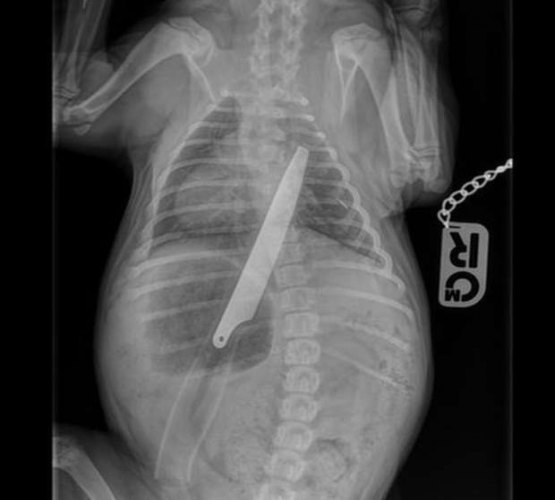

A cachorrinha Macie tem apenas doze semanas e sua dona, Irene Pailsey, a levou à emergência do hospital veterinário PDSA, na cidade de Glasgow, na Escócia, ao perceber que o animal estava engasgado.